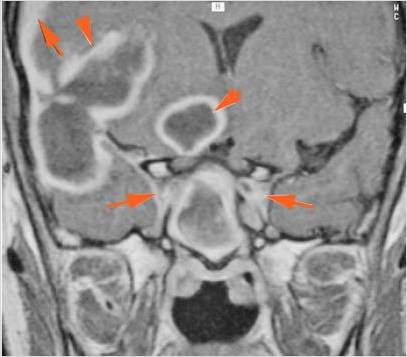

There is a subperiosteal fluid collection or abscess along the boney walls of the anterior or middle cranial fossa. [Yes/No]

There is an epidural fluid collection or abscess along the boney walls of the anterior or middle cranial fossa. [Yes/No]

There is a subdural fluid collection or abscess along the boney walls of the anterior or middle cranial fossa. [Yes/No]

There is a subdural fluid collection or abscess along the falx cerebri or within the tentorium. [Yes/No]

There is evidence of thrombus, thrombophlebitis or other occlusive or inflammatory process of the cortical veins, sphenoparietal sinus or sagittal sinus. [Yes/No]

There is evidence of thrombus, thrombophlebitis or other occlusive or inflammatory process of the cavernous sinus. [Yes/No]